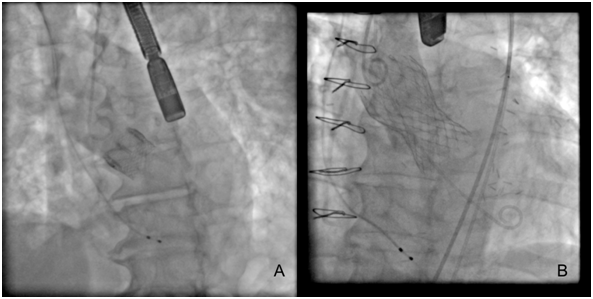

There are several approaches to transcatheter aortic valve replacement which include transfemoral, transapical, transaxillary, transubclavian, transcarotid, transcaval, and transaortic. The most common approach is transfemoral (Figure 1) and it appears to be safer in observational analyses than alternative access.18 An important determinant for transfemoral access is size of the iliofemoral circulation and its trajectory, as measured on a pre-operative CT scan. Patients with smaller iliofemoral vessels can develop more vascular complications.19 There is a trend, in selected cases and using transfemoral access, to perform the procedure without general anesthesia, intubation and surgery dissection. If patients do not have suitable vascular anatomy for transfemoral access, then an alternative approach can be undertaken in hybrid cardiovascular suites, which allow for integration of interventional cardiology and cardiac surgical techniques. The transfemoral vascular access for TAVR is the best choice for the procedure and improves the patient’s functional recovery.20 The size reduction of the delivery catheter of several TAVR systems has therefore increased the proportion of patients suitable for the transfemoral approach. For example, The Core Valve Evolutes R (23, 26, 29 mm; Medtronic, Dublin, Ireland) and SAPIEN 3 (23, 26 mm; Edwards Life sciences, Irvine, CA, USA) can be implanted using 14 Fr Inline sheath (Medtronic) or expandable-sheath technology, respectively. These simple systems can facilitate transfemoral TAVR in vessels as small as 5.5 mm (SAPIEN 3) or even 5.0mm (Evolut R).

Figure 1 Fluoroscopic views of TARV procedure with Edwards SAPIEN XT device (transfemoral vascular access) A. Positioning of a TAVR device in the aortic root B. The release of TAVR device balloon-expandable C. TAVR device balloon-expandable in an appropriated position (Images of our own files of cases).